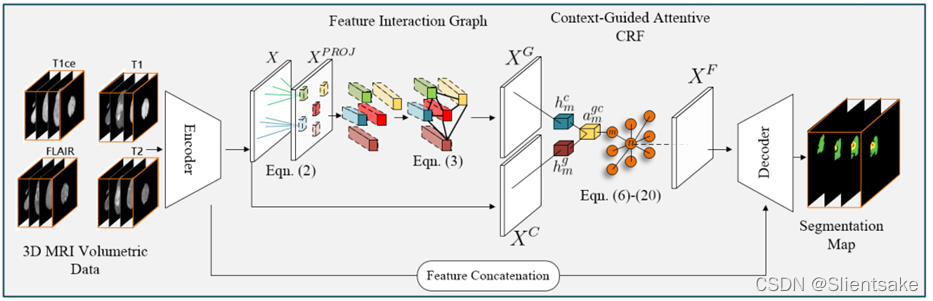

首先详细描述了所提出的特征交互图。然后作者引入了新的特征融合模块CGA-CRF,它可以选择性地聚合来自不同上下文的特征,并学习生成最优的特征。最后,将CGA-CRF中的平均场更新描述为序列卷积操作,使网络实现端到端训练。所提出的分割框架如图2所示。补充B总结了作者提议的CANet的训练步骤。

图2:提出的上下文感知网络的结构

与之前的工作不同的是,提出的CANet可以通过对特征交互图进行推理来隐式捕获长期的关系信息,这在文献中还没有得到充分的研究。这两个上下文(特征交互图和卷积)都使用来自共享编码器主干的中间特征映射X∈RN×C作为输入,其中N=H×W×D为中间特征映射中的特征实例总数。C是特征维数。图上下文在特征交互图空间XG∈RN×C中生成表示,卷积生成坐标空间表示XC∈RN×C。

CGA-CRF设计的主要理念是利用最终表示XF∈RN×C和中间特征表示X与辅助长程关系信息XG之间的关系,生成与MRI图像相关联的最优分割图。生成的交互空间具有其卷积特性XC,不同于直接连接XF= concat(X, XG, XC)或元素求和XF= X +XG+XC,作者的目标是通过一个新的条件随机场学习一组潜在特征表示XF。由于XC和XG在学习XF过程中可能做出不同的贡献,作者采用了注意机制的想法,并将其推广到CRFs的门节点。门节点可以调节信息流,发现不同上下文和潜在特征之间的关联。(公式字母不太规范,详情请参考具体论文)